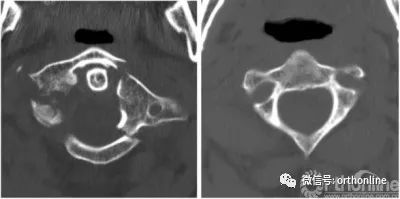

2014年5月,一名50岁男子因车祸入住我院。颈椎计算机断层扫描(CT)显示寰椎前弓及后弓多处骨折,侧块后1/3处分离(图1,左)。患者出现严重的颈部疼痛,当移动头部时疼痛剧烈,除此之外,无神经系统症状。同时合并有脑外伤、左侧额、颞部线性骨折以及头部软组织损伤,使我们在很长一段时间内无法使用Halo架固定。

最初,我们计划使用Harms技术进行C1-C2固定,用螺钉将寰椎碎裂的侧块融合。然而,病人的解剖特征使得这一方法不可行:其椎动脉位于C2椎体右侧,使右侧无法进行关节融合术。而C2右椎弓根、峡部、弧形部体积小,也使C1-C2的后路螺钉固定技术无法实施(图1,右侧)。由于这些限制,我们采用了前路经寰枢关节交叉螺钉固定技术(图2)和后路的Magerl技术[7]。

图1

图1案例1:颈椎术前CT扫描,左C1椎体多节段骨折,C2椎弓根、关节旁变薄,C2侧块的前缘两侧变薄;CT,计算机断层扫描

A 50-year-old man was admitted to our department in May 2014 after a car accident. Cervical spine computed tomography (CT) scans revealed multiple fractures in the anterior and posterior arcs of the atlas and abruption of the posterior third of its lateral mass (Fig.1,left). Clinical symptoms included severe cervical pain that increased dramatically when the patient moved his head; otherwise, he was neurologically intact. The concomitant traumatic brain injury, linear fracture of the left frontal and temporal bones, and soft tissue wound on the head prevented us from using the Halo device for an extended period of time. Initially, we planned to perform C1-C2 fixation using the Harms technique and fusion of the shattered lateral mass of the atlas with a screw. However, the patient’s anatomical characteristics prevented this. The location of the vertebral artery on the right side of the C2 vertebra made it impossible to perform transarticular fusion on that side. The small size of the C2 right pedicle, pars interarticularis, and arc also made it impossible to use the posterior screw fixation technique of C1–C2 on the right side (Fig.1,right). Due to these limitations, the combined anteroposterior atlantoaxial fixation technique with contralateral screw insertion (Fig.2) and Magerl trajectory[7]was performed.

Fig. 1 Case 1: pre-operative CT scan of the cervical spine. Left multisplintered fracture of the C1 vertebra. Right thinning pedicle, arc, and parsarticularis of the C2 vertebra as well as bilateral thinning of the anterior lip of the C2 lateral mass. CT computed tomography